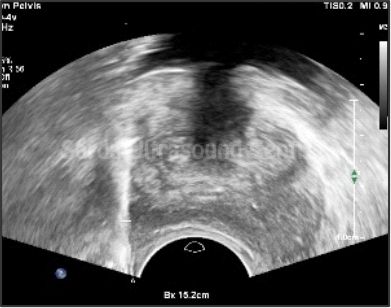

Our facility offers comprehensive range of ultrasound-guided interventions such as FNAC, biopsies, injections and aspirations, ensuring precise and safe treatment for our patients.

With Detailed pre-procedure councelling, High resolution ultrasound machines, Significant experience in using ultrasound for guided procedures, maintainance of sterile environment ensuring highest level of safety; we are committed to providing the highest standard of care for all ultrasound guided interventions.